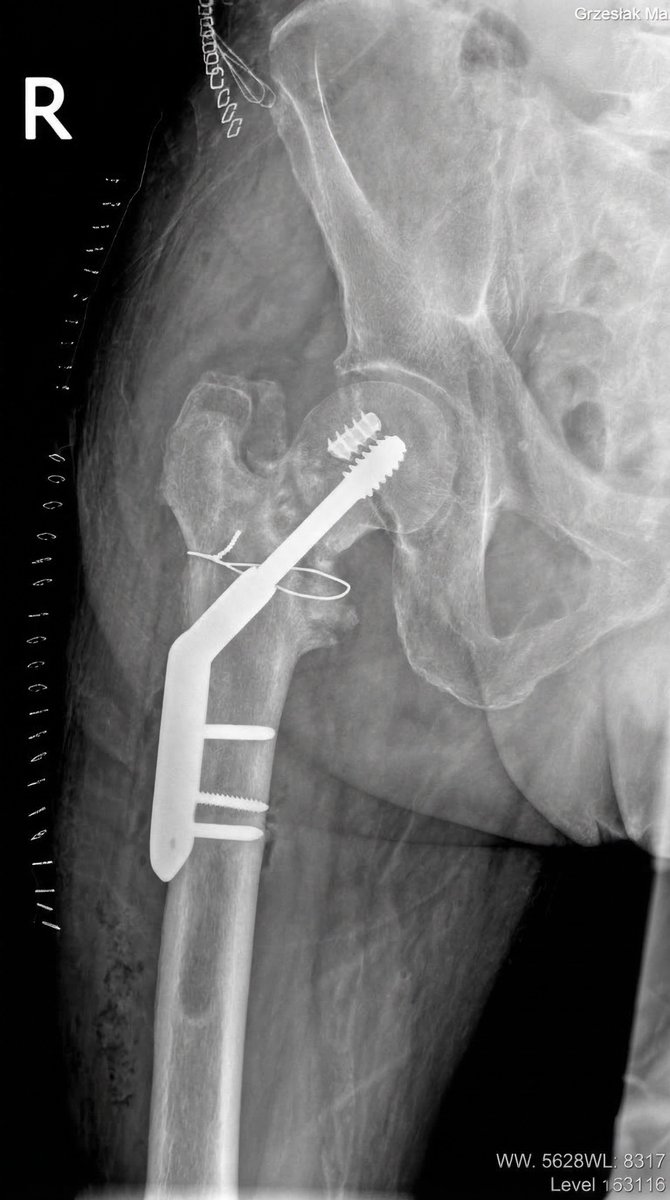

@traumaticum @ImprezowyKotek @orthobullets @orthotraumamd I see why a DHS… has the compression option that not all nails have, and it’s easier to add antirrotation or extra fixation screw in case needed. Also may let you correct valgus using the implant instead of forcing you to have it reduced before nail insertion. I like it.